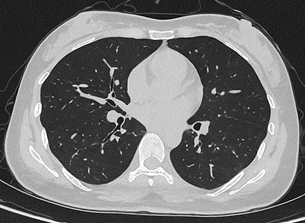

联影uCT Ultima扫描的0.2mm肺部超高清成像,扫描剂量低至0.1mSv

目前,华西厦门医院已基于该设备完成第一批患者扫描。“光子计数能谱CT的临床落地,是我国创新能力的重要体现,真正实现了对国外 ‘卡脖子’技术的突破。光子计数能谱CT实现了大幅降低辐射剂量,让患者CT扫描更安全。我们在临床案例中看到,设备不仅低剂量且高清,肺结节依然清晰可辨,临床价值十分突出。设备将在华西厦门医院的全链条、全生命周期的健康管理服务中发挥重要作用。”华西厦门医院党委书记廖志林说。